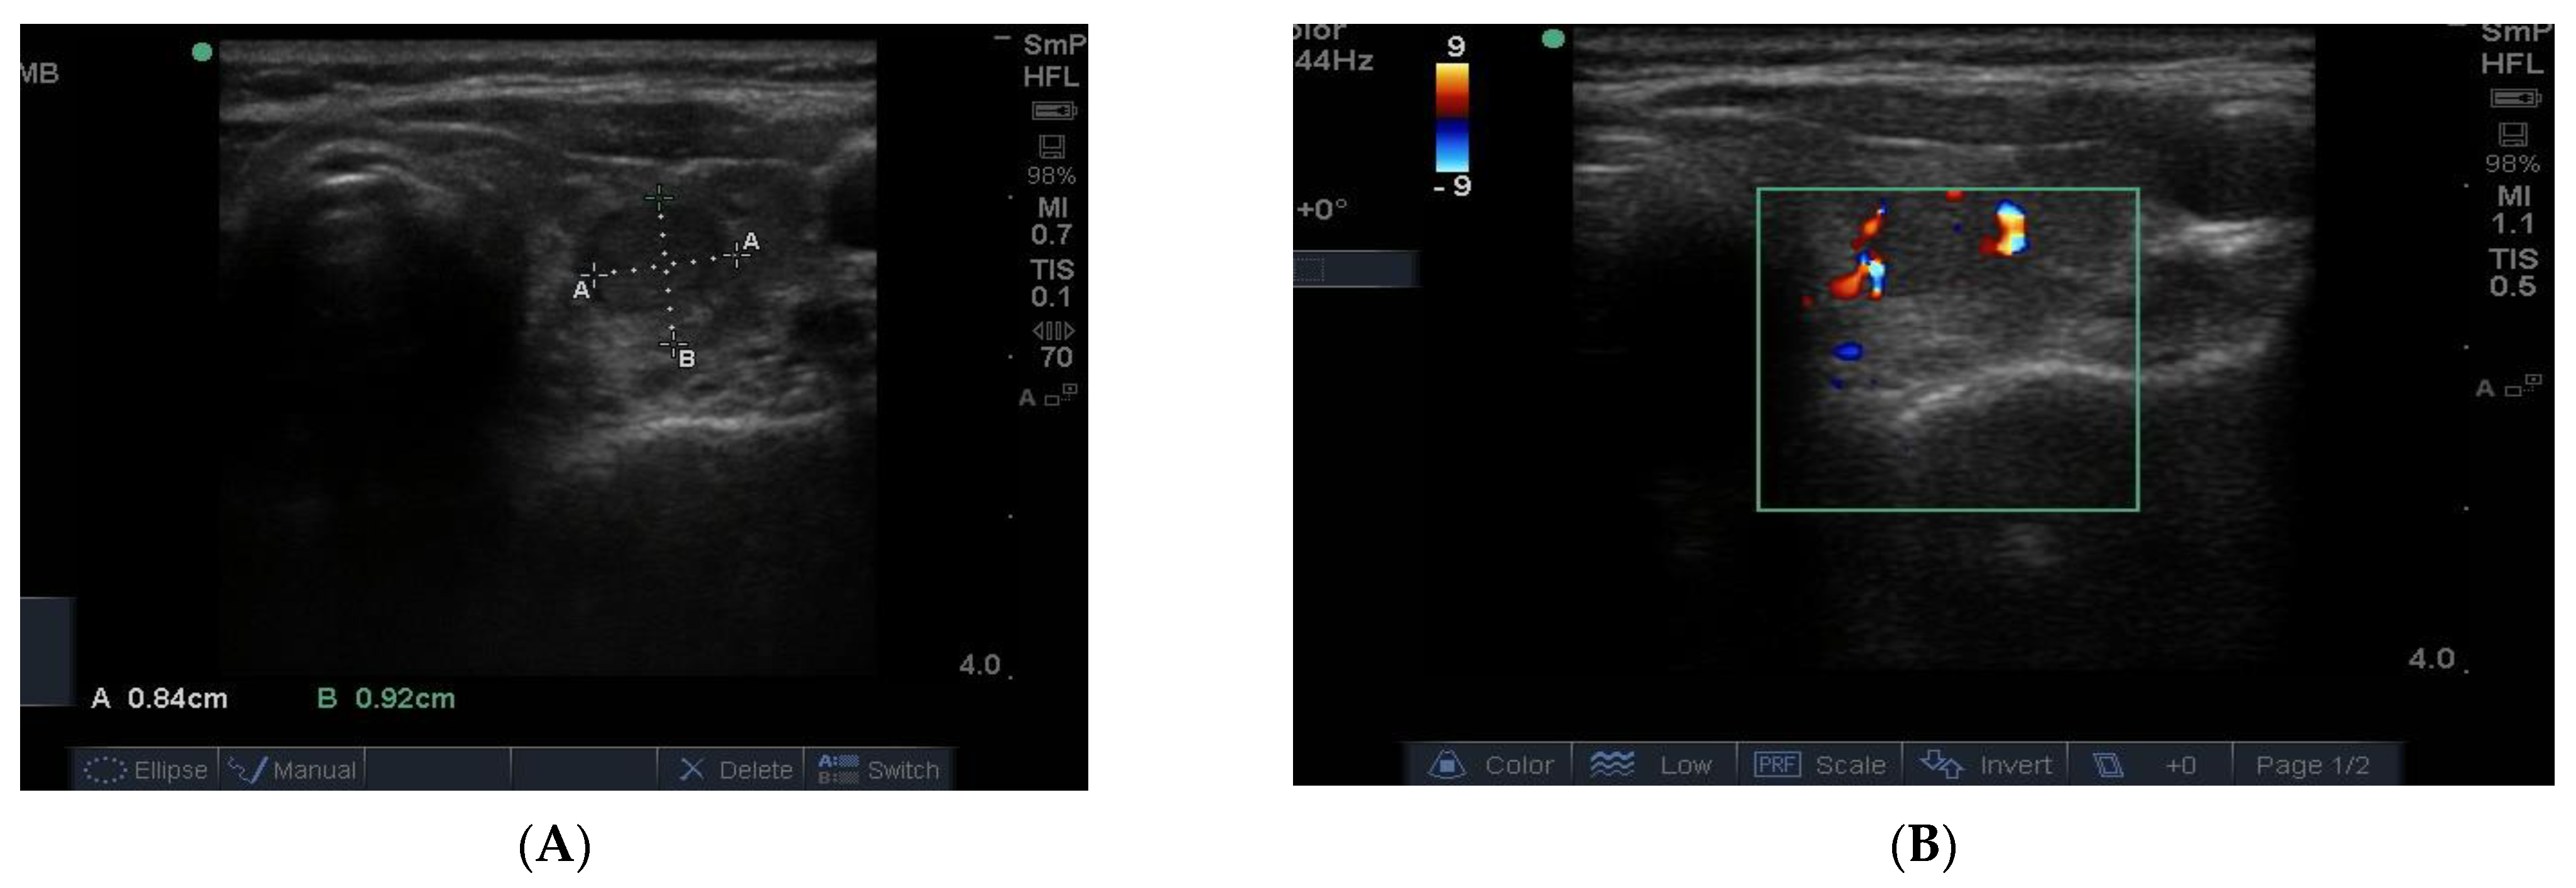

The blood supply to thyroid nodules is an important feature to be documented in the course of real time ultrasonography. There are three types of vascularity to be discussed. Firstly, the so-called hypoechoic halo surrounding a benign nodule is caused by compressed blood vessels which can be seen when the “colour” button is engaged. An example of this is seen in Figure 9A. Secondly, the degree of vascularity around the outside of a nodule is reflective of its activity and prominent blood supply around a nodule maybe a sign of thyroid cancer (Figure 9B) [8] but can also be present around nodules shown by biopsy to be benign. It has recently been shown that blood vessels within a nodule, especially if it has other suspicious features (Figure 9B), may be a reliable sign of cancer [9].

Figure 9.

In Figure 10 is shown matching images of a benign nodule without (A) and with (B) blood flow in the halo around the nodule.

Figure 10.

A small 8 mm benign nodule in the left thyroid lobe shown as an ultrasound image (A) and with surrounding vascularity in (B).